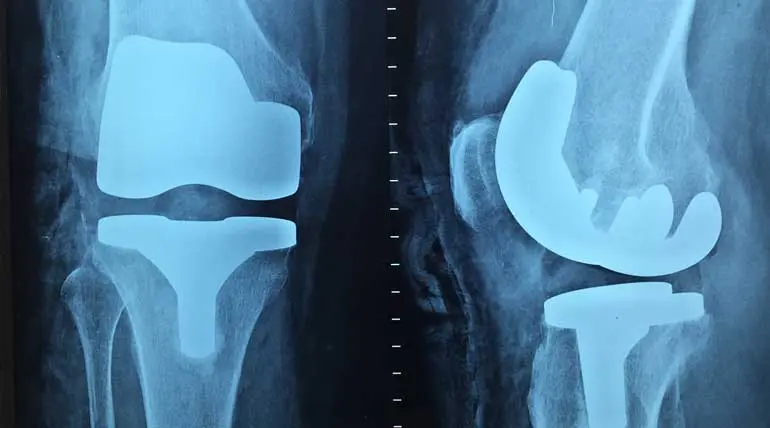

Knee surgery details that help to have a happy life: Many people do their knee surgery either too late or too early, confirms a new study. 90 % of people wait too long, and 25 % do premature knee surgery in the US is the finding of the study.More than 630 million people or 15 % of the population are

Knee surgery details that help to have a happy life: Many people do their knee surgery either too late or too early, confirms a new study. 90 % of people wait too long, and 25 % do premature knee surgery in the US is the finding of the study.

More than 630 million people or 15 % of the population are affected by osteoarthritis. Hence this study published on January 13 in Bone and Joint Surgery journal gains importance.

• Artificial knees fixed by early operations wear out within the next 20 years

• To operate again is near to impossible and also the outcome is not that of the first knee surgery